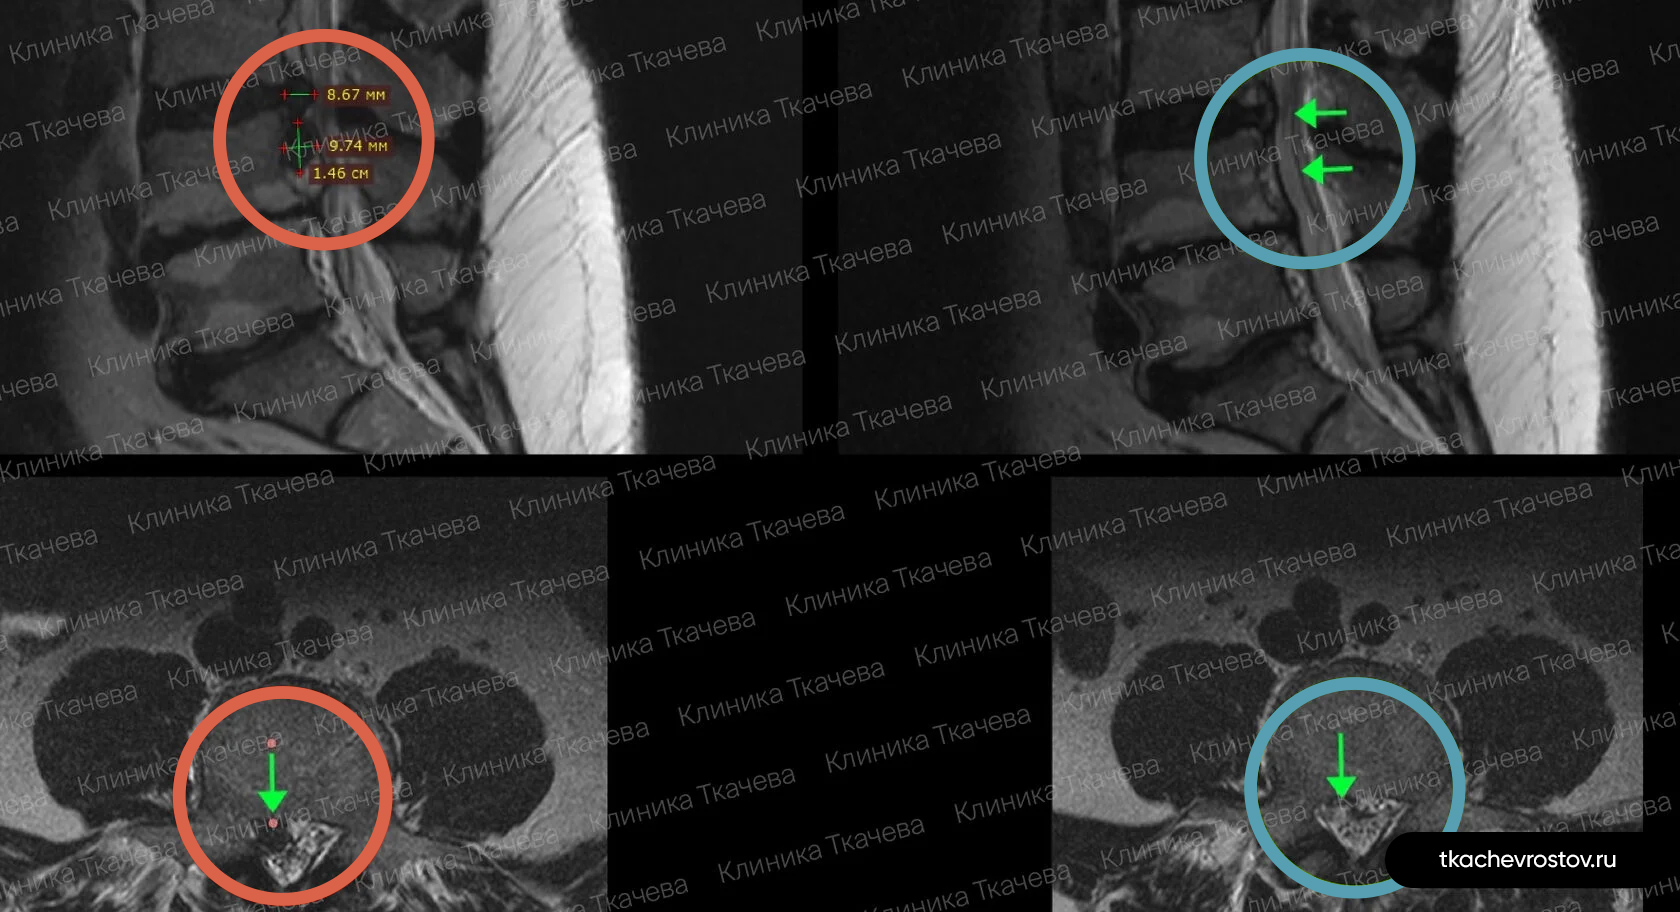

Грыжа в поясничном отделе L4-L5

Мужчина. Межпозвонковая грыжа в сегменте L4-L5 1.5 х 1.7 см с абсолютным стенозом позвоночного канала. Никакое лечение не помогло, отправили вначале к психиатру, а потом к нейрохирургу.

ДО:

- Интенсивная боль в пояснице, с эпизодическими прострелами

- Ограничение движений в пояснице

- Нарушения сна

- Снижение бытовой и социальной активности

ПОСЛЕ 1 курса:

✓ Наступила частичная резорбция грыжи

✓ Наступило улучшения общего состояния.

ПОСЛЕ 2 курса:

✓ Наступила полная резорбция грыжи

✓ Небольшое восстановление высоты межпозвонкового диска (регенерация пульпозного ядра)

Лечение грыжи заняло 8 месяцев. Было проведено 2 курса лечения по 12 дней.